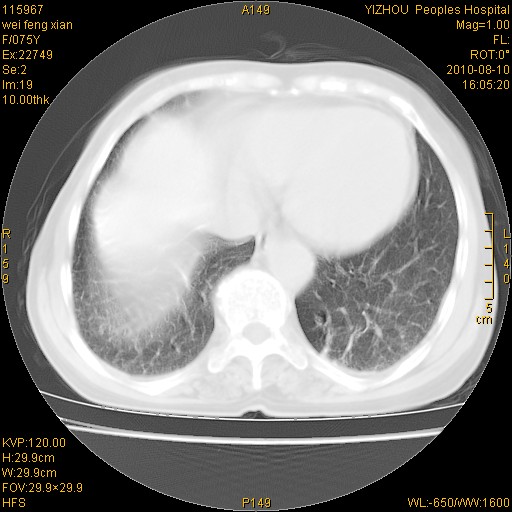

标题: CT28313:两肺弥漫性病变 [打印本页]

标题: CT28313:两肺弥漫性病变

女,75岁,患者反复头昏乏力面色苍白3年,再发10天入院。临床贫血查因。

双肺间质增生并右肺上叶炎性改变,不除外右肺上叶结核病肺内播散

考虑右肺上叶炎症合并双肺结核可能性大,建议上传纵隔窗ct图片。

双肺结核可能性大

考虑尘肺并结核;右上肺支气管扩张!

结核、尘肺、支气管肺泡癌都不能除外

右肺上叶继发性肺结核伴肺内血型播散!

考虑右肺上叶继发性肺结核伴两肺播散。